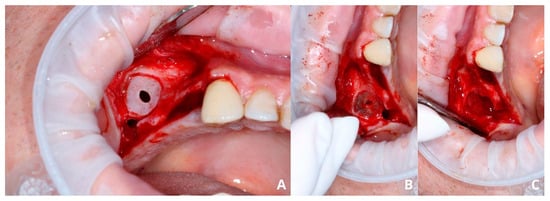

After elevating the mucoperiosteal flap (Figure 9A), a minor, about 3–5 mm wide osteotomy window is opened simply to allow biopsy (Figure 9B) and remove the cyst’s lining (Figure 9C,D). The perforation will not exceed the size of the minor window as the Schneiderian membrane remains safely attached to the bone. Afterward, a second, major osteotomy window is made around the minor one (Figure 10A). The existing perforation should be located in the center of the major window. Then, the bone ring is gently elevated and detached from the Schneiderian membrane (Figure 10B,C). Elevation should start from the center of the ring, not from its margin, since if the new perforation appears on the sidelines, it will be almost impossible to manage properly. From this point, the whole procedure is similar to the one described above: elevating the Schneiderian membrane, managing its perforation, and completing the augmentation.

Figure 9. Preparing for the first osteotomy. Elevation of a full-thickness flap (A). Creating a smaller window and aspirating the retention cyst’s yellow content (B). Removal of the cyst’s lining, firstly with narrow suction (C), then gently with tweezers (D). The perforation will not enlarge more than the diameter of osteotomy, as the periosteum is still attached to the bone, therefore remains safe.